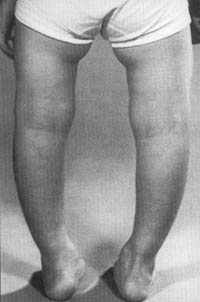

Una vez que un niño con raquitismo empieza a pararse, a caminar y estar activo, desarrolla nuevas deformidades debido a la característica blanda y débil de los huesos. La deformidad más común son las piernas en arco (Foto 34); con menos frecuencia se ven las rodillas juntas. Más serias, sin embargo, son las deformidades de la columna vertebral. Los cambios en la pelvis, aunque raramente son visibles, pueden ocasionar dificultades en el parto a las mujeres que han sufrido raquitismo en la infancia.

FOTO 34

Piernas arqueadas en un niño europeo con raquitismo